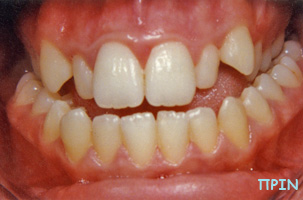

Οι μεικτές αυτές θεραπείες είναι εξαιρετικά εντυπωσιακές δεδομένου ότι ευνοούν όχι μόνο το στόμα και το χαμόγελο αλλά και το πρόσωπο συνολικά. Οι ασθενείς διανύουν ένα μακρύ δρόμο αλλά το τελικό αποτέλεσμα επηρεάζει τόσο θετικά την ζωή τους που αποζημιώνονται.